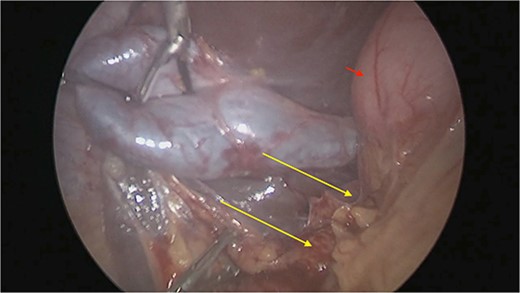

There were extensive perihepatic adhesions with involvement of the subhepatic space (Fig. 3). The initial intraoperative assessment was that this inflammation was secondary to a prior cholecystitis, but subsequent dissection revealed a pristine gallbladder (Fig. 4) with inflammatory adhesions in the pyloro-duodenal region (Fig. 5). All adhesions encasing the duodenum were lysed and the duodenum was kockerized (Fig. 6).

The gallbladder was dissected free of the dense adhesions. There was no evidence of previous cholecystitis. The stomach (short arrow) was spared of adhesions, but the first and second parts of the duodenum were encased (long arrows).